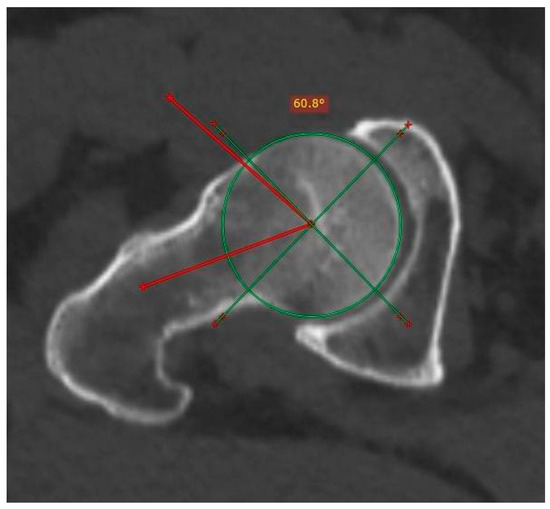

The Kolmogorov–Smirnoff test confirmed the normal distribution of data (p = 0.084). Regarding the interpretation of the mean comparison test, the p-values of the variables right Wiberg angle, left Wiberg angle, right excrescence, left excrescence, pincer, and cam suggested significant differences in the frequency of pincer-type FAI among the height groups (Table 1), where the compressing type with alpha angle was more common than non-compressing (Figure 4 depicts the measurement of the Alpha angle).

Figure 4.

Measurement of the Alpha angle in a patient with femoroacetabular cam impingement. The angle is obtained from the start of the middle femoral head by means of a linear stroke that runs through the center of the femoral neck and another to the point where the sphericity is lost at the junction between the head and the neck. The normal value is equal to or less than 50°.